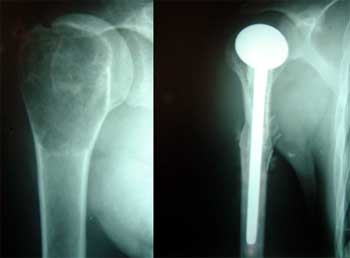

二、肱骨近端肿瘤

特殊的人工假体可解决肿瘤切除术后骨缺损这一问题,但手术时间需延迟,费用往往较高。大段的骨干缺损者甚至用特制的长柄型人工假体也难以置入固定。并发症较多,如假体松脱移位、不稳定、应力遮挡和受体骨吸收及肌腱、韧带等软组织无法对位缝合固定等。异体骨移植在人工关节置换手术中已经得到广泛应用。用“异体骨干人工假体”结构能解决软组织的对位缝合固定使关节稳定性增强,肢体的功能恢复良好。异体骨能有效地充填大块的骨缺损,减少了订做超长柄人工关节的需要。

一般应遵守的原则为牢固固定异体骨块,假体与移植骨之间应采用骨水泥固定,X线片显示自体异体骨愈合后再逐渐增加负重和运动。建议尽量采用深冻异体骨,因为深冻异体骨生物力学强度和成骨活性都优于冻干骨。术中应当将异体骨骨干部髓腔内的骨松质刮除,使骨水泥直接与皮质骨接触,增加结合强度,减少松动率。

1、术前明确诊断,准备长柄假体,准备大段异体骨。

2、肱骨近端肿瘤近端的准备。病变远端做骨膜下分离。距离病变最少3cm处肱骨横行截骨

3、肱骨近端肿瘤假体置入:采用与截除骨段同长度的异体肱骨近段,将异体肱骨头做后倾截骨,扩髓。选择试模插入异体骨段和远端髓腔,复位检查张力、活动度等。注意后旋角度,骨水泥固定假体。要求假体远端超过截骨线10cm以上